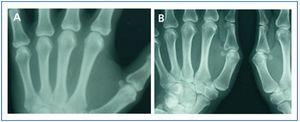

In January 2006, she presented serious SPTH, with notable increase in iPTH levels. The parathyroid ultrasound revealed an echo-rich pseudo-nodular structure in the posteriomedial area of the left thyroid lobe, compatible with parathyroid gland hypertrophy. A series of X-rays showed signs of hyperparathyroidism in the bones of both hands and wrists, with VC in radial and interdigital arteries. The mammography revealed multiple linear VC in both breasts (Figures: 1A, 2A, 3A and 4A; hand and mammary gland images in 2006).

During this period, the X-ray series showed that the interdigital artery calcifications had disappeared, and the bone appeared better structured (Figures 1B and 2B; hand X-ray, 2007). The mammography also showed regression of the VC. Initial linear calcifications were replaced by irregular calcifications (Figures 3B and 4B; mammary glands in 2007).

Figure 1. (A) Anteroposterior X-ray of left hand in 2006. (B) Anteroposterior X-ray of left hand in 2007

Figure 2. (A) Anteroposterior X-ray of right hand in 2006. (B) Anteroposterior X-ray of right hand in 2007